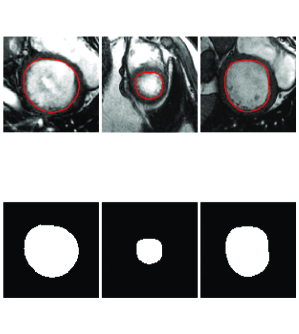

To better understand the role of each step, the outcome of the deformable model with no shape constraint (), deep learning (shape inference, Step 2) and the integrated deformable model and deep learning method (final step) for two typical images are shown in Fig. 8.

As seen in the left side of Fig. 8, the outcome of the deformable model without shape constraint (blue) leaked to surrounding tissues due to low contrast at the borders. Clearly this is not acceptable. On the other hand, the deep learning network (shape inference) provided a close contour (red) to the ground truth (green) with no leakage. This is due to the fact that the network has been trained using the ground truth data to look for the overall shape of the LV and not the intensity difference at the border. Finally, the integrated deep learning and deformable models brought the contour (yellow) closer to the ground truth. Similar behavior can be seen in the right side of Fig. 8 when contours tend to shrink due to presence of papillary muscles in the LV.